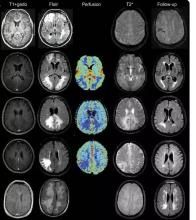

MRI可顯示多發性皮質和皮質下大的或小的淤點狀出血灶,患者如無出血史,則提示曾經發生過無症狀出血。MRI梯度回波(GRE)序列可顯示鐵沉積的證據,後者為陳舊性出血的表現。對於腦葉出血者,陳舊性淤點狀出血的證據有助於CAA的診斷。GRE-MRI還可用於監測疾病的進展、評估將來的危險性以及評價治療干預的效果。在基線水平時,GRE-MRI上發現的陳舊性ICH病灶越多,將來發生ICH、認知功能障礙、生活不能自理和死亡的危險性就越大。對於合併血管炎的患者,MRI可見到腦脊膜增厚。

只有在少見的CAA相關性血管炎患者中,血管造影才會發現異常。但在這類患者中,其特異性和陽性預測值不足30%。明確診斷仍需進行腦組織活檢(敏感性為53%,陰性預測值為70%)。鑒於CAA的某些特徵與血管炎相似,發現血管炎的特徵時應高度懷疑CAA。對於伴有認知功能迅速減退(數周或數月內)、嚴重頭痛及癲的出血性或缺血性卒中史的患者,應該考慮進行血管造影檢查。